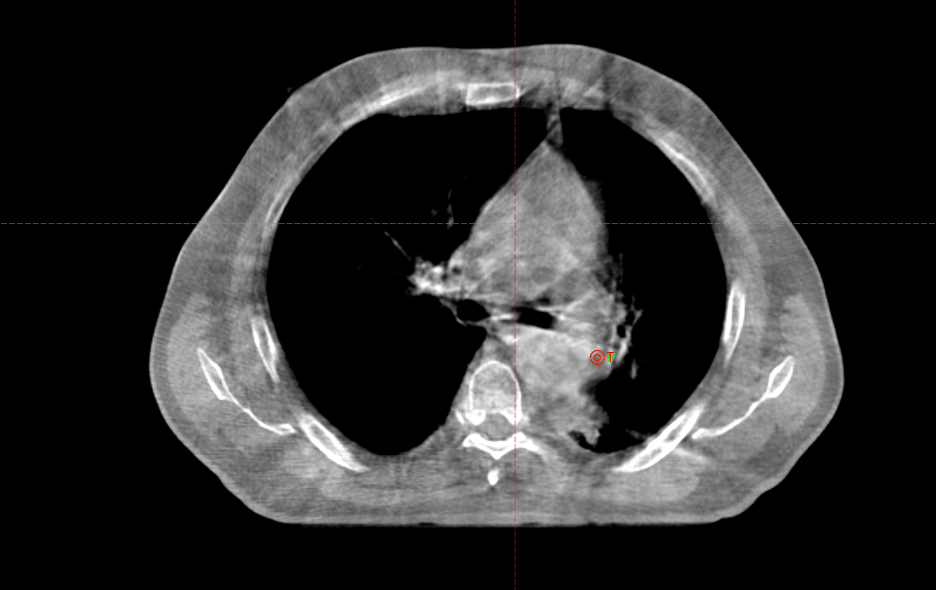

Заключение ПЭТ-КТ с ФДГ от 29.03.2022г:

- картина центральной опухоли левого легкого с признаками обструктивного пневмонита, мтс с поражением ипсилатеральных и подкаринальных лимфоузлов.

В воротах левого легкого определяется метаболически активный опухолевый узел с вовлечением главного, нижнедолевого, частично верхнедолевого бронхов, общими наибольшим размерами около 83 мм в аксиальной проекции и до 81 мм в краниокаудальной проекции, SUVmax=21.41. Опухоль располагается на расстоянии около 30 мм от киля трахеи с вовлечением левой легочной артерии (обхват около 50%) и тесным прилеганием к нисходящей аорте. Окружающая паренхима левого легкого с признаками воспаления. В правом легком очаговая и инфильтративная патология легких не определяется.Определяются метаболически активные медиастинальные лимфоузлы, наибольшими размерами/накоплением РФП: подкаринальной группы (7) до 10 мм, SUVmax=7.49; субаортальной группы (5) до 8 мм, SUVmax=4.70. Лимфоузлы ворот левого легкого четко не дифференцируются, вероятнее сливаются с основной опухолевой массой.

В воротах левого легкого определяется метаболически активный опухолевый узел с вовлечением главного, нижнедолевого, частично верхнедолевого бронхов, общими наибольшим размерами около 83 мм в аксиальной проекции и до 81 мм в краниокаудальной проекции, SUVmax=21.41. Опухоль располагается на расстоянии около 30 мм от киля трахеи с вовлечением левой легочной артерии (обхват около 50%) и тесным прилеганием к нисходящей аорте. Окружающая паренхима левого легкого с признаками воспаления. В правом легком очаговая и инфильтративная патология легких не определяется.Определяются метаболически активные медиастинальные лимфоузлы, наибольшими размерами/накоплением РФП: подкаринальной группы (7) до 10 мм, SUVmax=7.49; субаортальной группы (5) до 8 мм, SUVmax=4.70. Лимфоузлы ворот левого легкого четко не дифференцируются, вероятнее сливаются с основной опухолевой массой.